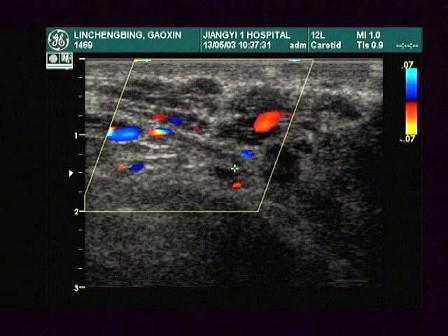

某患者阴囊根部增大,超声声像图如下,最可能的诊断为?(?)A.附睾炎B.斜疝C.精索静脉曲张D.隐睾E.精索鞘膜积液

问题 某患者阴囊根部增大,超声声像图如下,最可能的诊断为?(?)

选项 A.附睾炎 B.斜疝 C.精索静脉曲张 D.隐睾 E.精索鞘膜积液

答案 C